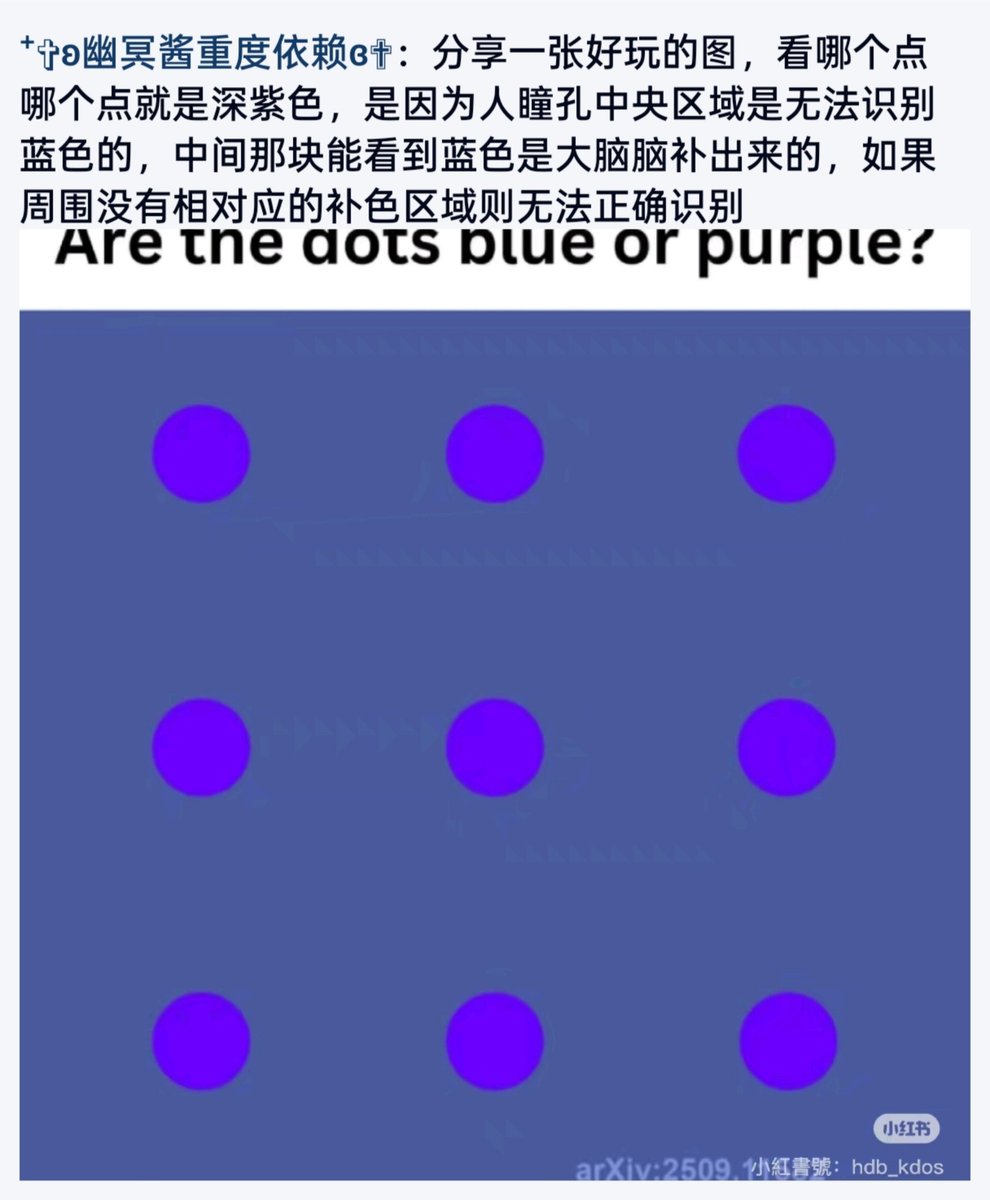

看上去像是为了描述某类特定效应而创造的术语(可能是nmda受体活性增强),用来对抗因NMDA受体拮抗剂(比如氯胺酮、DXM、PCP等)引发的解离体验(dissociation)。

看上去像是为了描述某类特定效应而创造的术语(可能是nmda受体活性增强),用来对抗因NMDA受体拮抗剂(比如氯胺酮、DXM、PCP等)引发的解离体验(dissociation)。